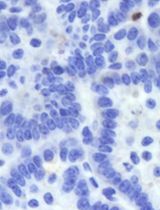

5. To analyze the tumor microenvironment after MWA, euthanize 3–5 additional mice following MWA and CAR-T-cell injection. Residual tumors should be harvested and assessed for CAR-T-cell infiltration by flow cytometry or histological staining.